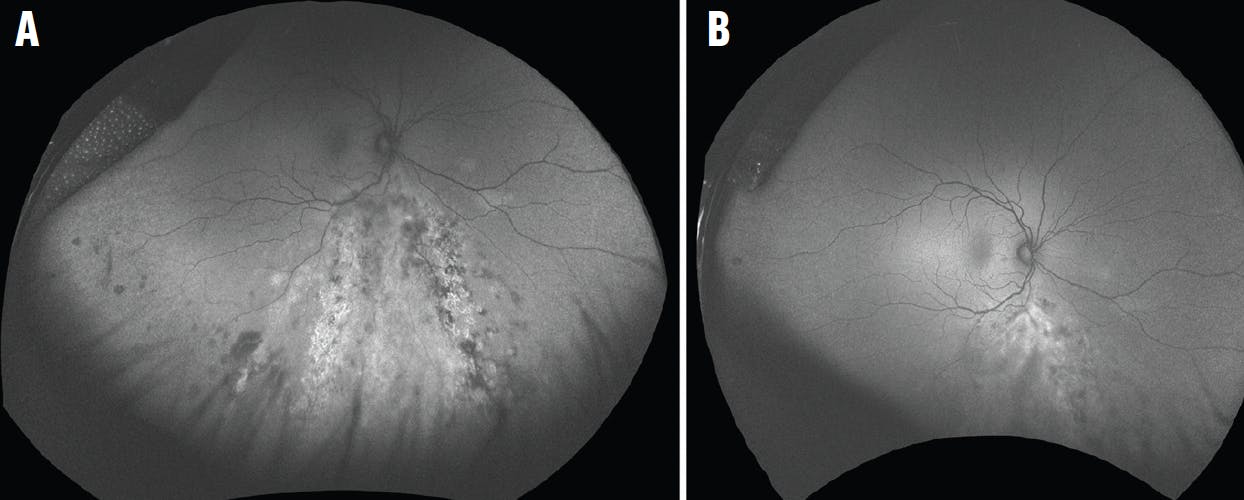

Ultra-widefield (UWF) imaging with a confocal scanning laser ophthalmoscope allows up to a 200° digital view of the retina. Just as with slit-lamp photos, UWF pseudocolor images can be critical in documenting the examination for comparison (Figure 2). Occasionally, these images can better highlight subtle examination findings, such as white dots, areas of early retinitis, and choroidal lesions. Furthermore, UWF pseudocolor images provide views of the peripheral retina in patients who would otherwise be challenging to examine due to a secluded pupil, significant photophobia, or age. When the pupil is very small, we find it helpful to get a view of the retina that is otherwise impossible at the slit lamp.

Figure 2. UWF pseudocolor images of a patient with cytomegalovirus retinitis before (A) and 3 weeks into (B) treatment.

Short-wave fundus autofluorescence (FAF) uses specific excitation wavelengths of light (green or blue) and generates images showing the emission signals of lipofuscin pigments primarily located in the retinal pigment epithelium (RPE) and photoreceptor outer segments. Thus, FAF can highlight areas of photoreceptor or RPE damage and inflammation of the choriocapillaris. In general, hyperautofluorescent lesions represent disease activity in most inflammatory maculopathies.2 FAF may also highlight areas of pathology that may have been missed on fundoscopy, such as in subtle outer retinal or choroidal lesions (Figure 3). Often, active infection shows up on FAF prior to being readily apparent on examination. However, sometimes the hyperautofluorescent lesions do not resolve even when the disease is inactive, so FAF images must be interpreted with care.

Figure 3. UWF green FAF image of a patient with cytomegalovirus retinitis before (A) and during (B) treatment.